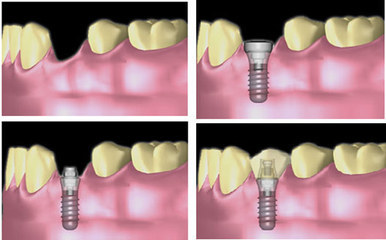

- 种植牙虽然只是一个小手术,说起来比较简单,但是实施起来需要顾客和多个医生共同的努力。那么,种植牙分几个步骤呢?说起来种植牙的步骤也很多,这就需要按部就班的进行,也需要医生和患者共同合同,才能节约时间达到满意的效果。

种植牙大致步骤如下:

1、种植Ⅰ期:指的是种植手术过程。

2、种植Ⅱ期:种植术后3-6个月,把愈合帽(healing cap)更换为愈合基台(healing abutment)的过程,目的是袖口形成。如果初期稳定性理想,Ⅱ期可以和Ⅰ期同时完成,即不用愈合帽,直接安装愈合基台。

3、种植修复:Ⅱ期后4-6个月开始修复,包括取模、加工厂制作、戴牙、调牙合。